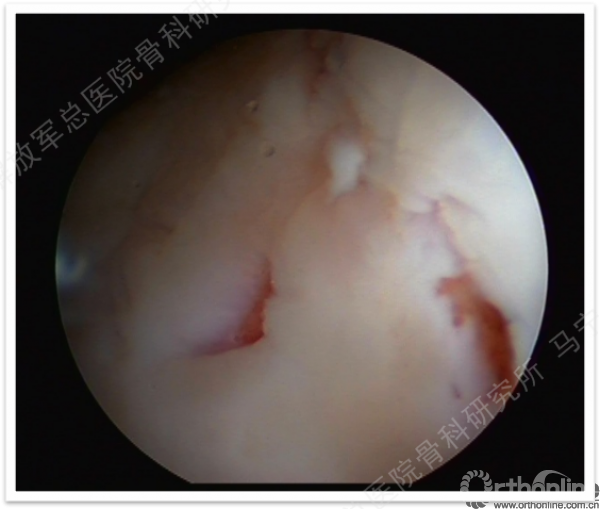

缺损部位的标记:根据关节镜下的检查评估来确定损伤部位,范围,以决定二次手术的切口部位。

软骨组织的获取:关节镜下观察关节软骨的股骨髁间非负重区的穹窿部位或股骨滑车区边缘非负重部位,清理周围的滑膜组织,应用髓核钳或鹅眉凿获取患者关节软骨100-200mg